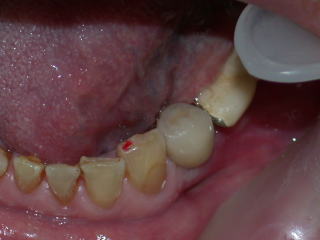

インプラントトランスファーを装着した状態です。

アバットメントを装着します。